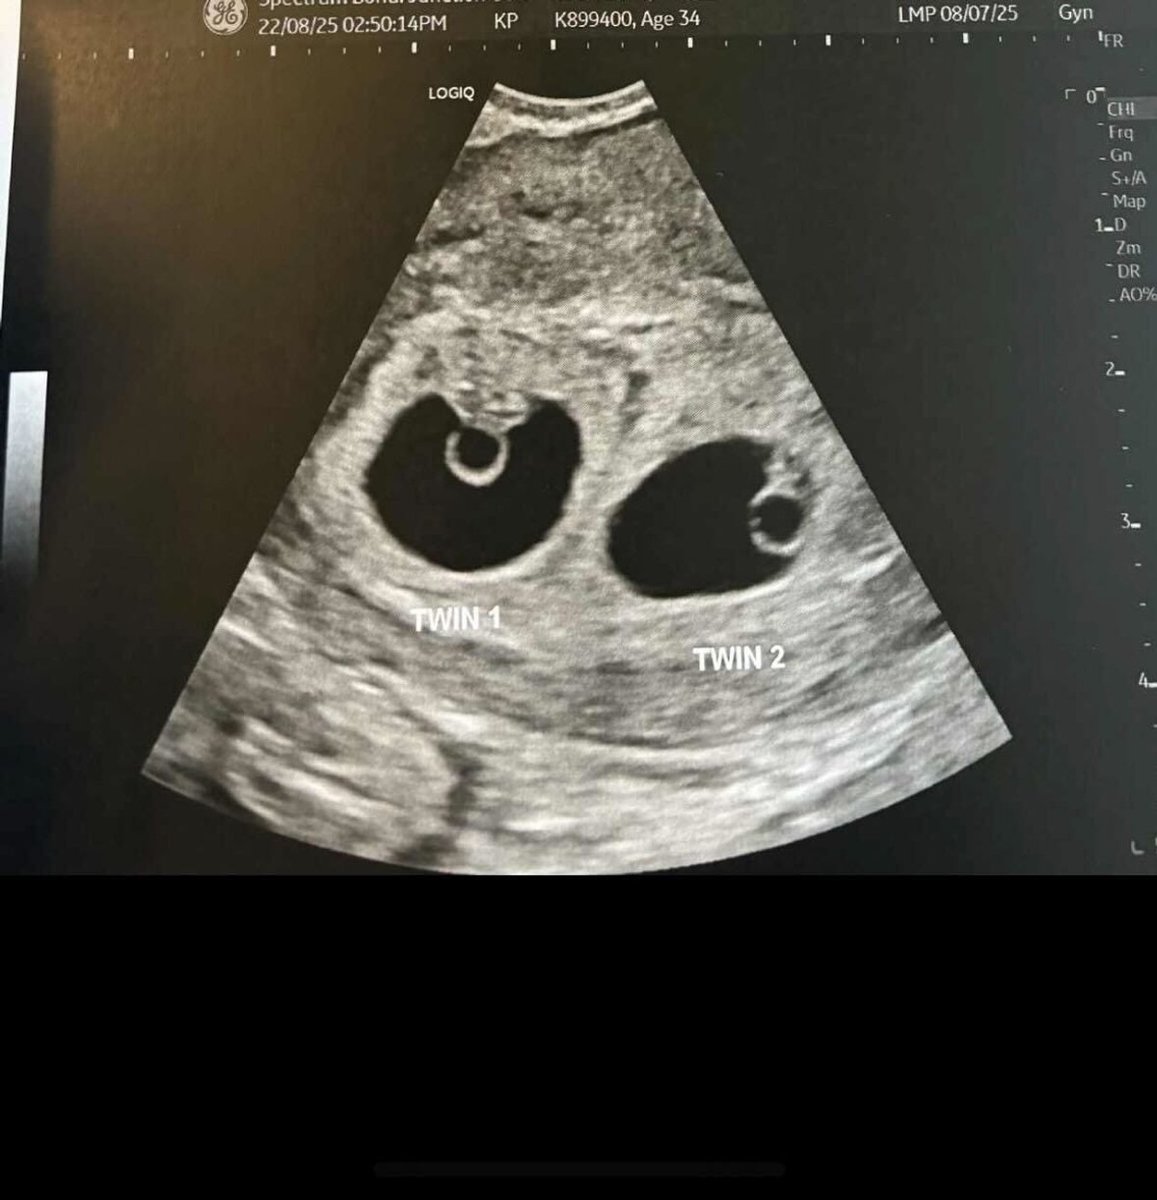

The ultrasound technician went very quiet a few minutes into my seven-week dating scan.

I was alone and nervous. I'd experienced a pregnancy loss and had fallen pregnant the next month, which is to say I was expecting bad news. I had come desperate to hear a heartbeat. When my husband later messaged me, asking, "is there a heartbeat?", I didn't know how to reply. There was an issue with his use of the singular noun.

The internal commenced and I stared at the ceiling. Minutes passed. "Alright," she said, "You can see, there's a heartbeat, there's your baby inside a sac…"